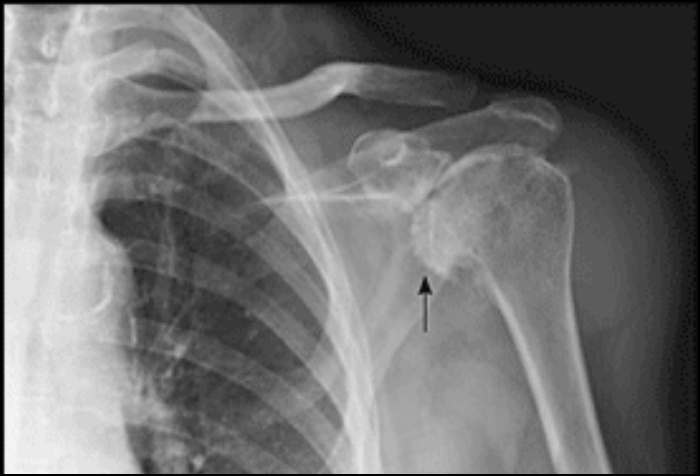

The shoulder is a ball and socket joint in the upper extremity that is in part responsible for the positioning of the hand in space. It is made up of the gleno-humeral joint, the acromio-clavicular joint and sternoclavicular joint. These joints are lined with cartilage (gristle) for smooth movement. Like every other joint in the body, the shoulder can suffer from wear and tear of the cartilage – arthritis. This is most commonly observed after middle age and it mainly afflicts the glenohumeral and acromioclavicular parts of the joint.

After a history and examination, the surgeon will perform an X-ray of the shoulder to help confirm the diagnosis. Treatment starts with activity modification (avoiding if possible the actions that cause pain), painkillers and gentle physical therapy as pain allows to maintain shoulder function and strength. If symptoms persist, judicious injections of steroid may be given, though not more than 2 in the same joint in a calendar year. If these measures fail to control symptoms then you and your surgeon should discuss joint replacement surgery.